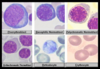

ID the cell

Proerythroblast

ID the cell

Metamyelocyte

ID the cells

Lymphoblasts

ID the cell

Band neutrophil

ID the cell

promyelocyte

ID the cell

monocyte

ID the cell

metamyelocyte